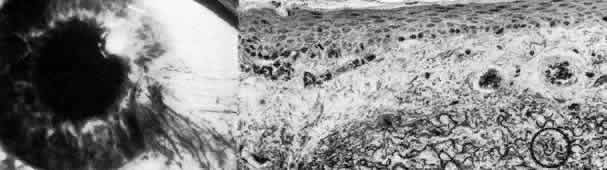

Fuchs' Dystrophy (Late Hereditary Endothelial Dystrophy)

Fuchs' dystrophy (Figs. 5 AND 17)185–189 is usually seen in the fifth or sixth decade of life, somewhat more commonly in women. It is bilateral and frequently of dominant inheritance.185,186,190 The fundamental defect is progressive deterioration of the endothelium. The endothelial cells in the adult human lack significant miotic capability, and as they undergo attrition, the surviving cell population must enlarge and spread to maintain an intact monolayer in order to remain functionally competent as a barrier and pump in maintaining corneal deturgescence. Thus, as in patients with cornea guttata, serial pachymetry and specular microscopy are helpful in following the disease process. Both discrete (guttate) and diffuse thickening of Descemet's membrane usually develop with progressive endothelial degeneration and dysfunction (Color Plate 1,K).187

Fig. 17. Late hereditary endothelial dystrophy (Fuchs). Top left. Clinical photograph illustrates epithelial bullae, scarring, and neovascularization, resulting from long-standing stromal edema. Top middle. Light microscopy demonstrates intraepithelial edema, thickening of the basement membrane, subepithelial bullae (*) and fibrocellular pannus with adjacent break in Bowman's layer (hematoxylin-eosin, × 350). Top right. Transmission electron micrograph of basal epithelial cells and Bowman's layer shows multilaminar basement membrane complexes (BM, the sequel of chronic epithelial edema (× 5000). Middle left. Transmission electron micrograph of posterior cornea shows unremarkable stroma and anterior Descemet's membrane, but remarkable thickening of posterior Descemet's membrane to 12 mm with additional superimposition of large guttata (G). The remaining endothelial cells (En) are severely degenerated and attenuated (× 5000). Middle right. By scanning electron microscopy, the comparable picture of disjointed, attenuated endothelium (En) and numerous exposed guttata (*) is apparent. Note the fibrous feltwork quality of the abnormal posterior Descemet's membrane (× 300). Bottom. High-magnification trans mission electron micrograph of guttata resolves its composition of fine filaments (circled), multiple segments of basement membrane material (*), and collagen in long-spacing configuration (arrowheads) (× 50,000). (Top left. Grayson M: Diseases of the Cornea, p 242. St. Louis, CV Mosby, 1979)

Clinically evident edema starts axially and spreads peripherally. As stromal edema progresses to involve the epithelium, microbullous elevations of the epithelium bring decreased visual acuity, and in time, bullous keratopathy erupts (Color Plate 1L). When these epithelial blisters rupture, the patient experiences a foreign body sensation or pain that may be relieved by lubricants, occlusion, or bandage soft contact lens. Ultimately, penetrating keratoplasty is required for both comfort and visual rehabilitation. In rare instances when keratoplasty is not indicated, cautery of Bowman's layer may give symptomatic relief. The course of Fuchs' dystrophy may be accelerated after cataract extraction or other intraocular surgery, and precautions should be exercised to minimize intraoperative trauma.

On histologic examination, the sequelae of chronic epithelial and stromal edema are prominent. Anteriorly, abnormalities of the basement membrane adhesion complexes develop because of repeated lift-off of the edematous epithelium.188 There are occasional breaks in Bowman's layer, and subepithelial debris and fibrovascular pannus collect in the zone of bullous edema. The most striking abnormality is diffuse thickening of Descemet's membrane (often to 20μm or more) with posteriorly projecting excrescences, corresponding to clinically apparent guttata. Histologic evidence of abnormal endothelial cell function is apparent many years before the clinical signs of corneal guttata and thickened Descemet's membrane appear.191